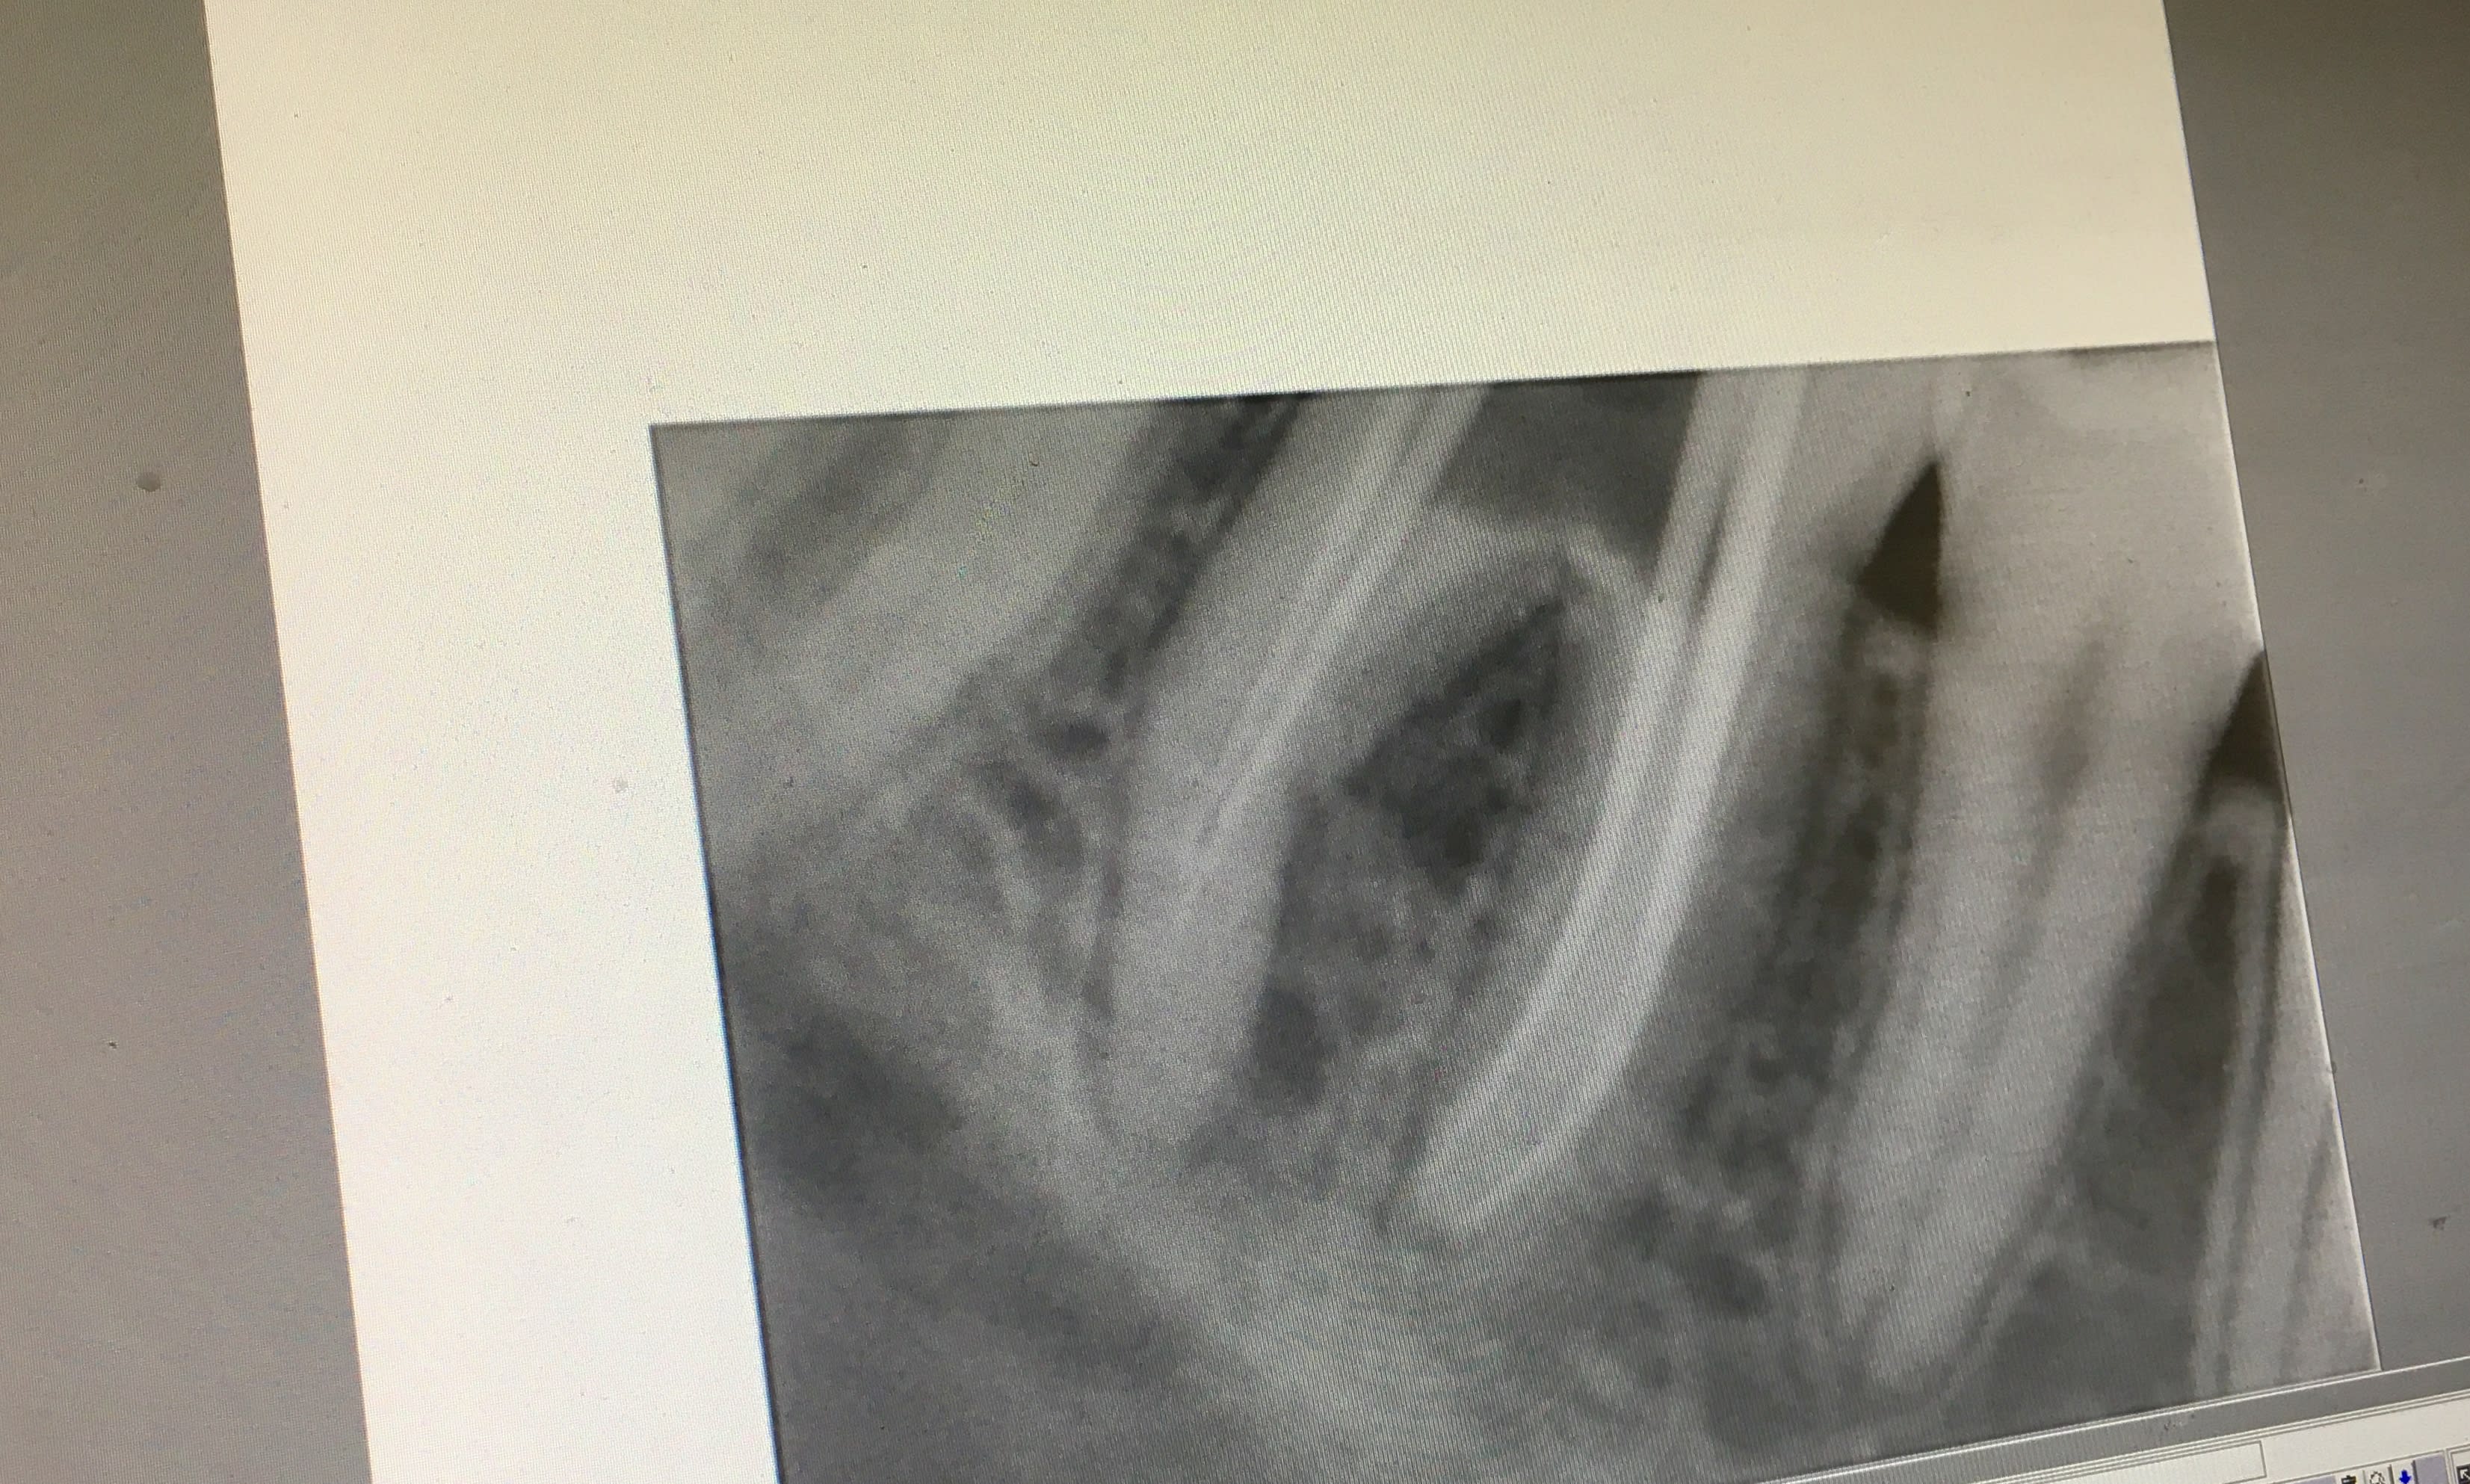

J’ai commencé une devit sur la 46 mais le soucis est que mes limes dans les disto se bloquent à 3-4mm de l’apex

il y a parfois des coudure qu'on ne peut pas passer , même en précourbant

dans ce ca j'irrigue encore plus que d'habitude, je passe les ultra sons largement pour activer l'hypochlorite , et je n'insiste pas au risque de faire une fausse route , et j'obure , puis je temporise avec une couronne et wait ans see

En manuel, tu précourbes bien, tu reperes bien ta courbure avec le marquage sur le stop de ta lime.

La j'ai repris les canaux mesiaux en manuel, lime k/H en alternance... l'ancien prat avait buté dans la courbure. La difficulté c'est biensur de retrouver les canaux et surtout de na pas continuer dans la fausse route.